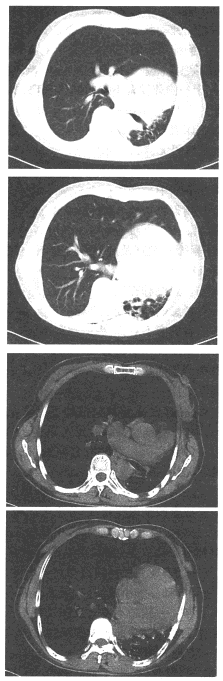

17、单项选择题

女,52岁,左侧背痛1月,胸部CT如图,最可能的诊断为()

女,50岁,查体发现纵隔向左移位,行胸部CT扫描如下图。

A.纵隔向左移位